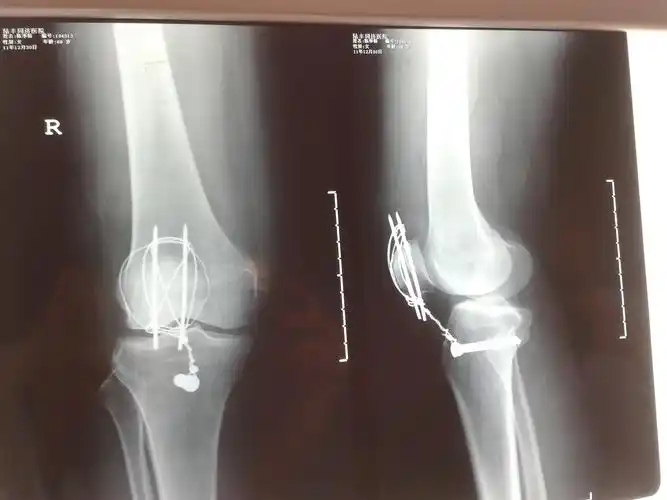

髌骨骨折.这样有错吗.